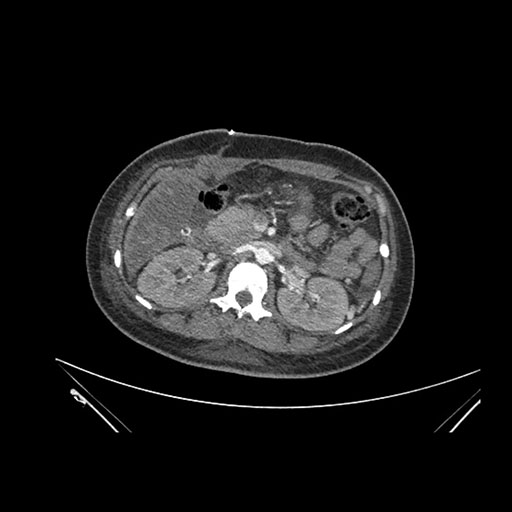

Imaging Analysis

Look through the patient's CT scan to identify any areas of concern for the necessary procedure.

Axial Venous

Based on initial findings, which issue(s) would you be most concerned about?